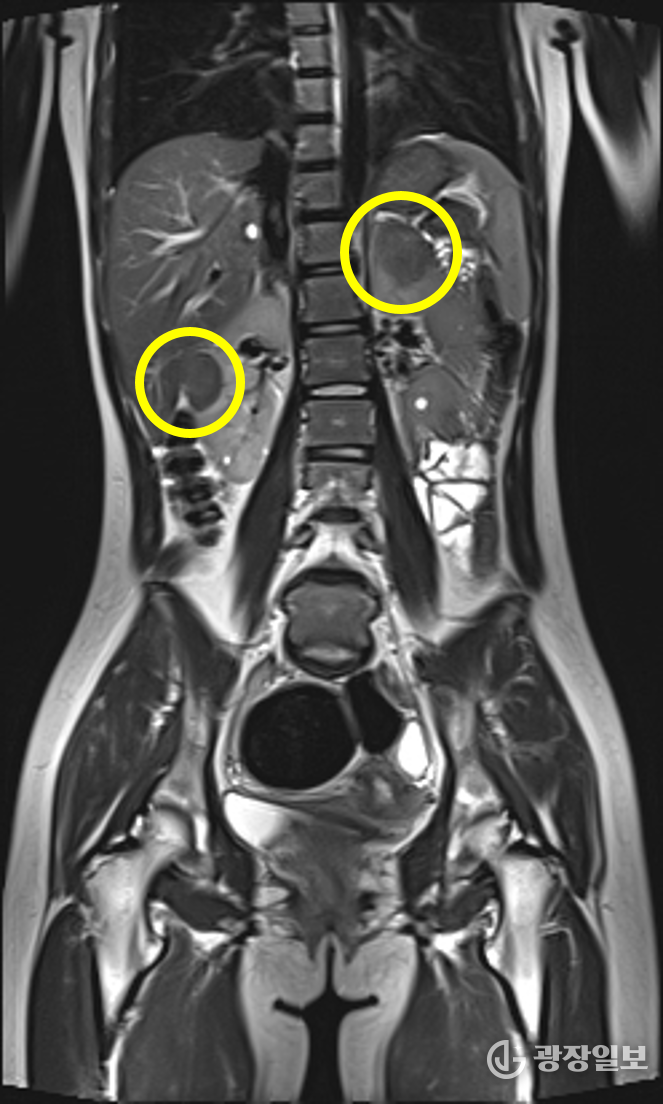

결절 경화증(tuberous sclerosis complex, TSC)은 종양억제유전자의 돌연변이로 인해 세포 증식이 조절되지 않고, 뇌·신장·피부·심장·폐 등 여러 장기에서 양성 종양이 발생하는 유전 희귀질환이다.

가장 흔한 증상인 뇌전증 발작과 피부의 혈관섬유종, 백반증을 비롯해 자폐스펙트럼장애, 인지장애, 신장 낭종, 폐세포 증식증 등 다양한 증상이 연령과 상관없이 나타나기 때문에 조기 진단과 장기적 관리가 필수적이다.